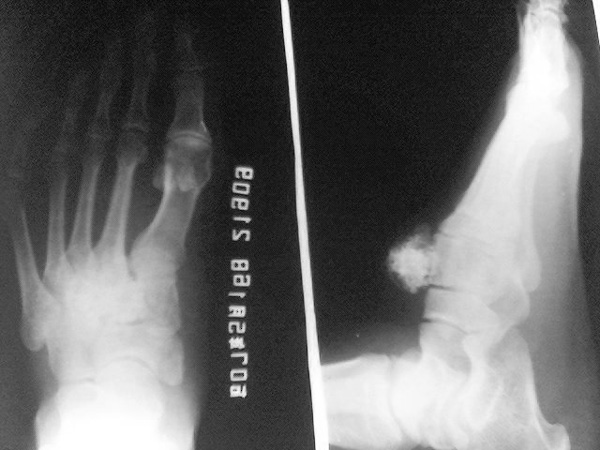

病人 男性  50岁   右足背肿块15年  近感疼痛加剧

手机拍的  不太清    足背软组织可见局限的多发斑点状及不规则状钙化影   请大家赐教

菜花状骨软骨瘤,建议这个病人做ct检查排除恶变,这种骨软骨瘤最容易恶变。